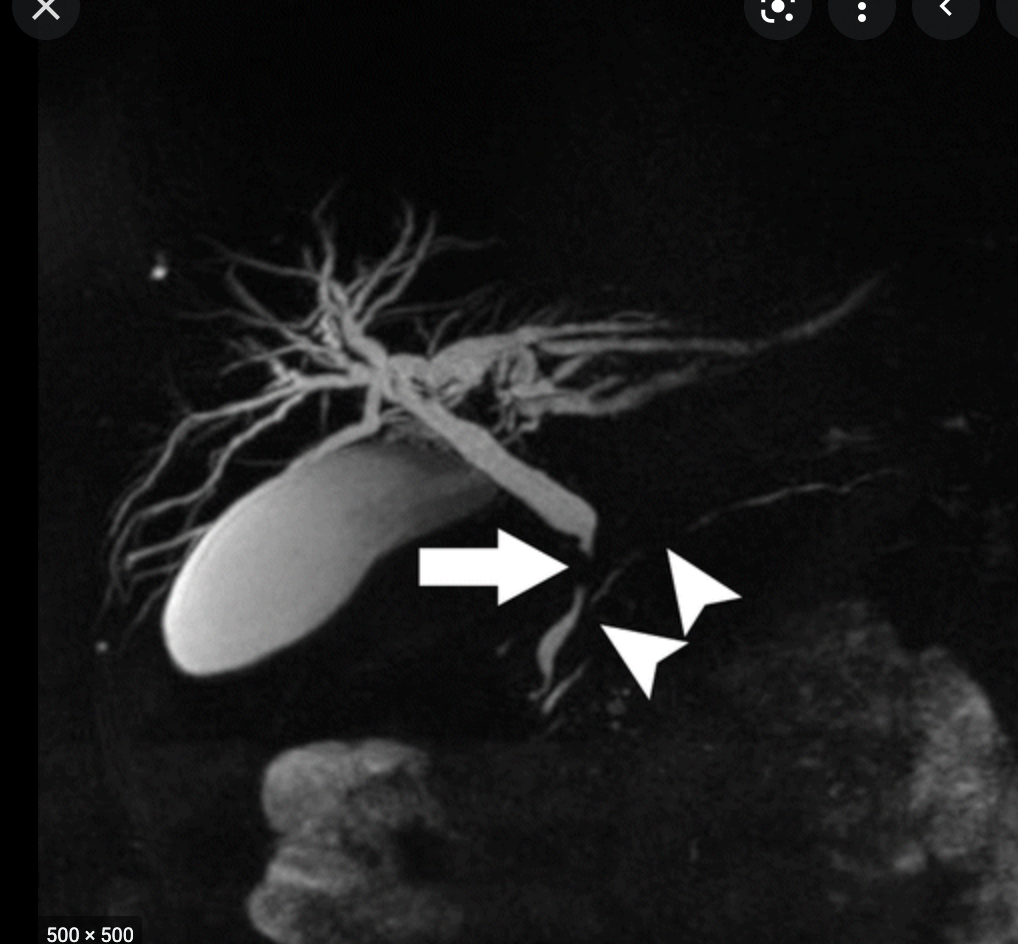

What is MRCP

- Fat sat T2 imagines of the upper abdo

- bile is hyper intense

- images of the biliary and pancreatic ducts can be rendered by maximum signal intensity projection recons (MIPS)

- Common indications

- unsuccessful ERCP

- ERCP contraindicated

- biliary-enteric anastomoses

- chledochojejunostomy

- billroth II